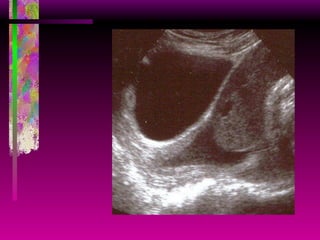

Acretismo Placentario Diagnóstico Ecográfico: Adelgazamiento (< de 1 mm) o ausencia de la zona hipoecoica miometrial en el segmento inferior (signo de mayor sensibilidad). Espacios lacunares vasculares en la placenta (queso suizo). Adelgazamiento, irregularidad o disrupción de la interfase vesico-uterina. Extensión del tejido placentario a través de la serosa uterina (percretismo).

Acretismo Placentario Diagnóstico Ecográfico: 27 sem

Acretismo Placentario Diagnóstico Ecográfico:

Acretismo Placentario Diagnóstico Ecográfico: Es el método más económico y difundido. Comparativamente es el de mayor precisión: -  Sensibilidad:  86 %  -  VPP:  80 %   -  Especificidad:  92 %  -  VPN:  84 % Si el área hipoecogénica retroplacentaria es  2 mm o más, el Doppler y la RNM no aportan mucho más. Sin embargo, la información anatómica no siempre es concluyente.